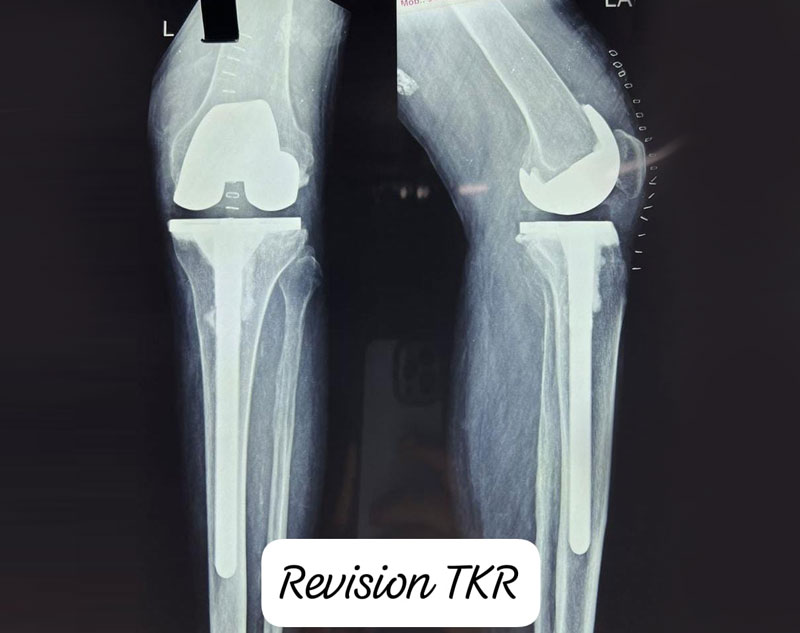

Revision knee replacement is a more complex procedure done when a previously implanted knee prosthesis fails or wears out. It involves removing the old prosthetic components and replacing them with new ones.

Both procedures aim to restore function, reduce pain, and improve the patient's quality of life, but revision knee replacement is typically performed after a primary replacement fails or develops complications.